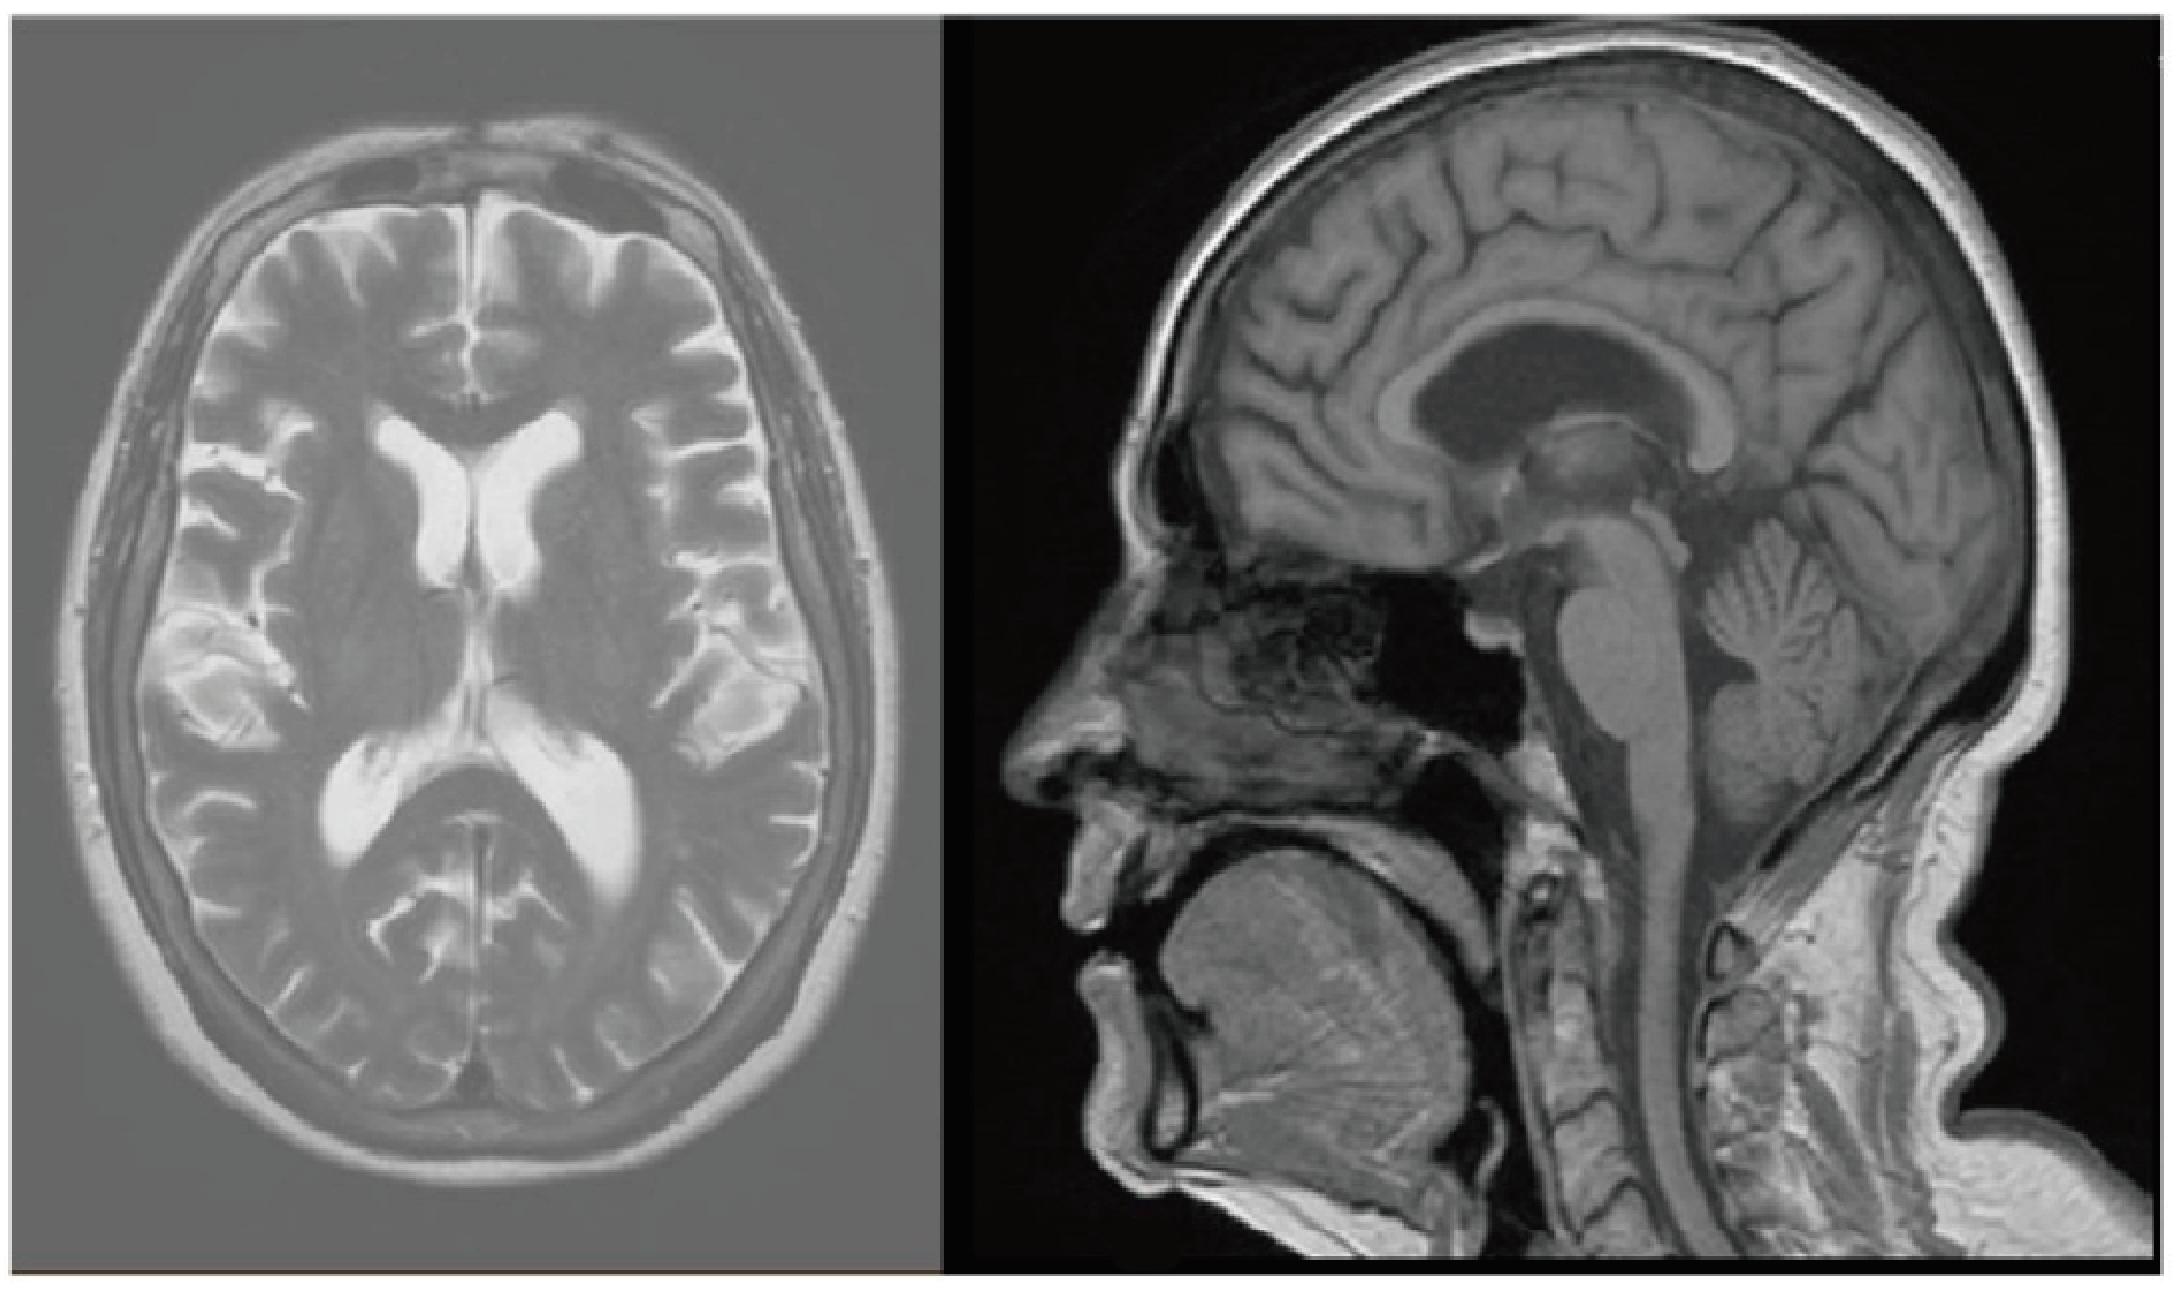

Two weeks after the administration of the third cycles of treatment, the patient presented with sweating, hot flashes, vertigo, headaches, pain in both arms and systemic chills. It was decided to discontinue the treatment, and she was hospitalized for further investigation. MRI of the spine and head was performed, which showed no evidence of distant metastasis or other abnormalities (Figure 1). Bacterial growth was ruled out by negative results of urine and cultures. CT scan of the total body did not indicate the source or the cause of the fever. Echocardiography revealed no signs of myocarditis or pericarditis, with normal range of ejection fraction. Due to bilateral upper extremity paresthesias and arm pain, the patient was referred for neurological consultation, and a diagnosis of suspected autonomic neuropathy from pembrolizumab therapy was made.

Figure 1. MRI of the head revealed no pathologic findings or evidence of metastasis.